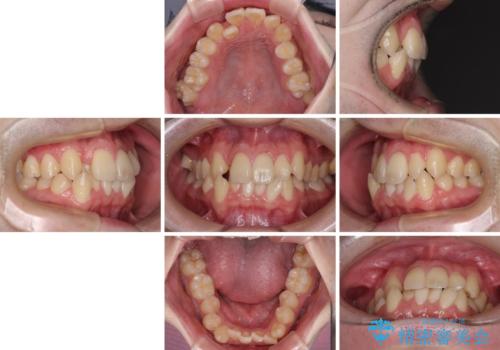

全顎的なクロスバイト 補助装置を用いてワイヤー矯正

- 八重歯や奥歯の噛みにくさを気にして来院された患者様です。

前歯のクロスバイトや八重歯の他に、左右最後臼歯のシザーズバイト(鋏状咬合)が認められました。

シザーズバイト改善のために補助装置を使用しながら、ワイヤー装置にて全体の歯列を整えることとしました。